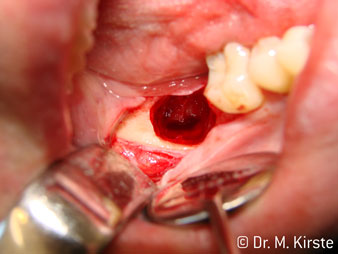

El nuevo diseño de los rodamientos dentro del cabezal de la pieza de mano garantiza el funcionamiento silencioso de la fresa, en la separación del diente o la raíz (Fig. 4-9) se muestra una impresionante imagen de corte sin efectos de impacto.